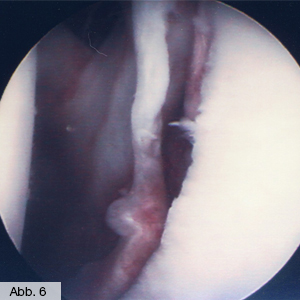

Eine typische Sportverletzung beim Schultergelenk ist die Schulterluxation. Häufig kommt es hierbei zu einem Abriss der Knorpellippe, die die Gelenkpfanne vergrößert und stabilisiert (Labrum). Hierdurch kommt es dann immer wieder zu Luxationen. Durch eine arthroskopische Reparatur des Labrums (Abb. 6) kann dieser Schaden beseitigt werden, gleichzeitig muss häufig die Schulterkapsel gerafft werden. Oftmals geht eine Schulterluxation auch mit einem Riss der Rotatorenmanschette einher. Auch diese Verletzung sollte operativ behoben werden, was meist durch eine arthroskopische Naht erfolgen kann.